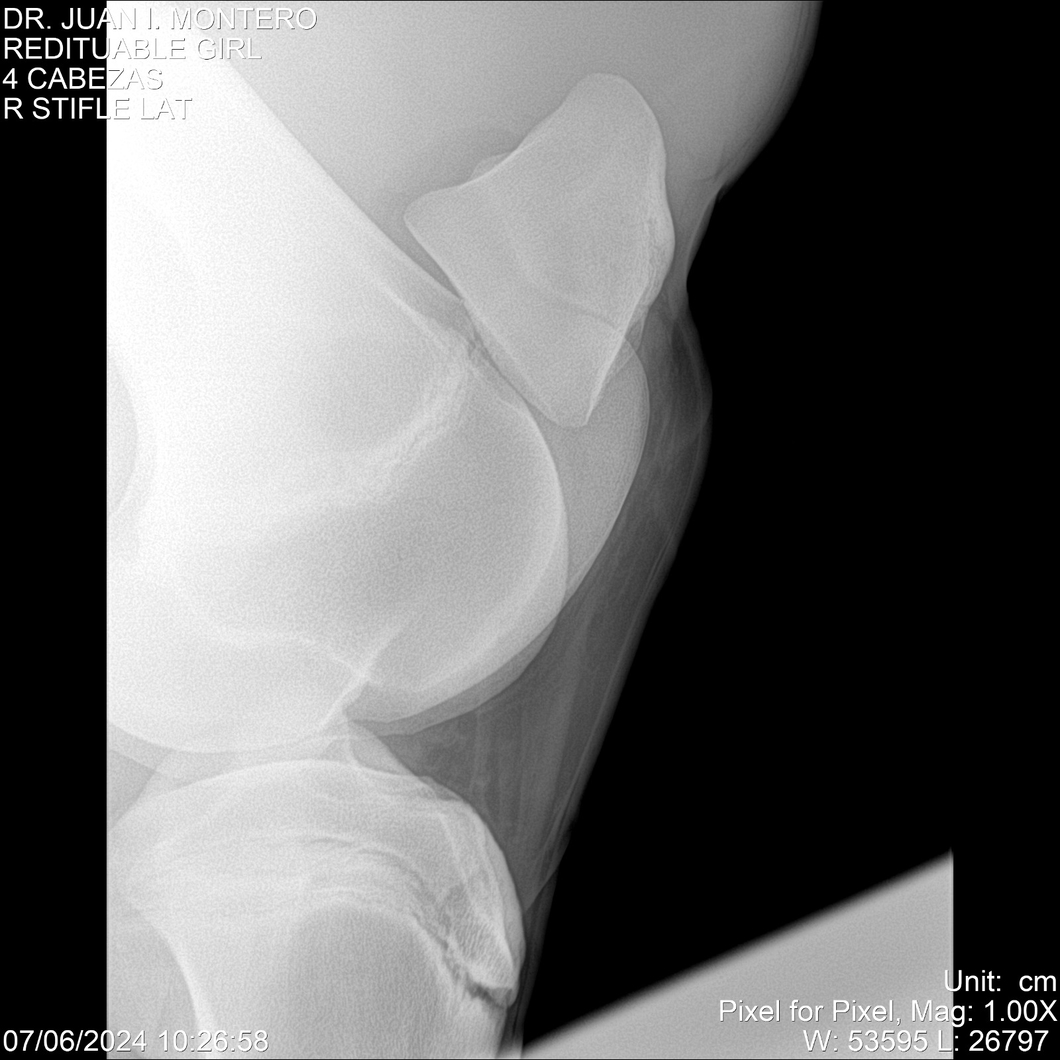

LOTE 19, REDITUABLE GIRL Lote Anterior Volver al remate Lote Siguiente Ficha Contacto Montevideo - Ficha del Lote Identificador: #281096 Categoría: Yeguarizos Montevideo - 79 Visualizaciones ClicData Contacto Empresa: Abelenda N. R., Walter Hugo Nombre*: Teléfono* : E-mail* : Mensaje Enviar Registrese gratis Este contenido Exclusivo está disponible sólo para usuarios registrados Ingresar